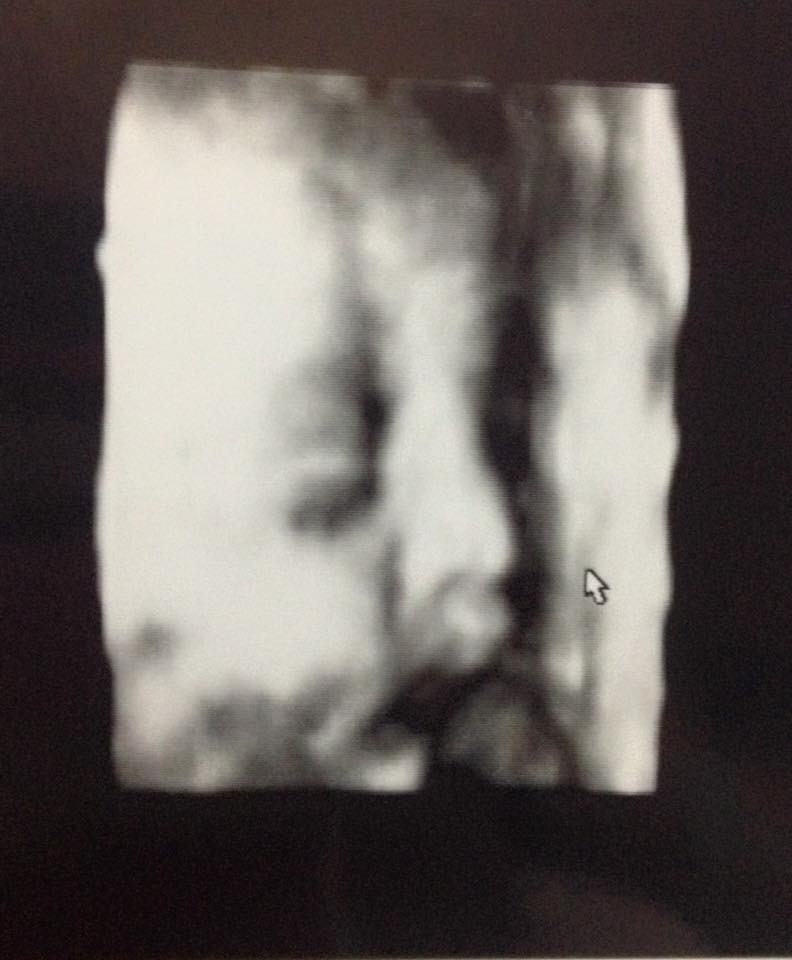

La imagen del feto que utilizaba el doctor Oliva.